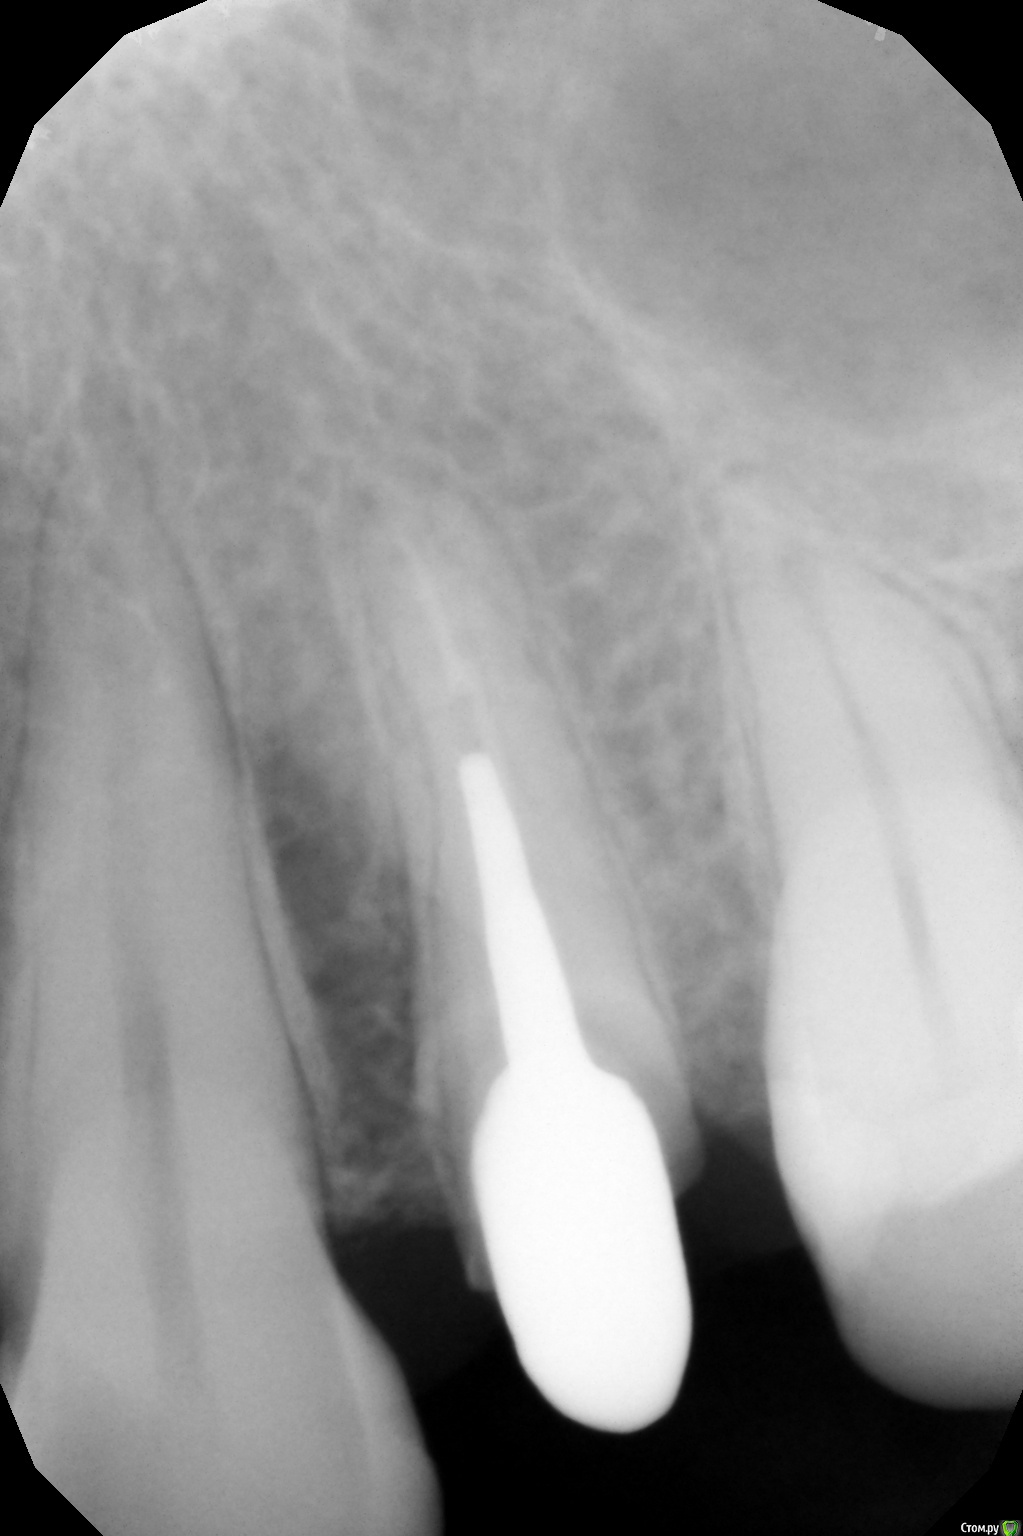

mikedolev Опубликовано 31 августа, 2016 Поделиться Опубликовано 31 августа, 2016 24 зуб, подготовили канал под вкладку, расширили и убрали старый пломбировочный материал, каналы оказались параллельны, сделали не разборную вкладку и посадили на цемент.Потом на снимке я увидел что между пломбировочным материалом и вкладкой есть зазор (с 0,5 мм наверное).Стоит ли волноваться на эту тему? врач считает что зазоры для вкладок это норма. "там цемент".Также видно потемнение слева между 24 и 25, у десны, но ведь так низко периодонтита не бывает? Ссылка на комментарий

Гарриевич Опубликовано 1 сентября, 2016 Поделиться Опубликовано 1 сентября, 2016 Если Вы о зазоре в корневом канале, то в принципе вообще не критично 1 Ссылка на комментарий

St. Опубликовано 1 сентября, 2016 Поделиться Опубликовано 1 сентября, 2016 Стоит ли волноваться на эту тему? врач считает что зазоры для вкладок это норма. "там цемент". Также видно потемнение слева между 24 и 25, у десны, но ведь так низко периодонтита не бывает? Ничего критичного не вижу. 1 Ссылка на комментарий